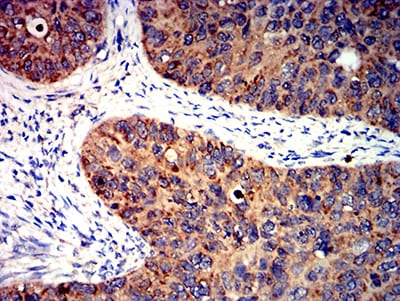

- Immunohistochemical analysis of paraffin-embedded human cervical cancer tissues using BCL2L2 mouse mAb with DAB staining.